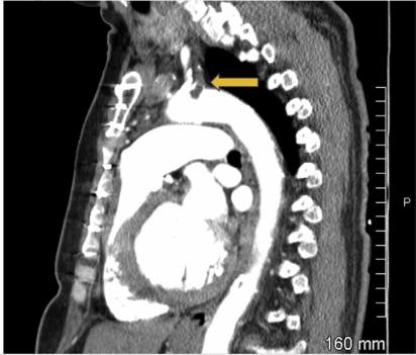

图1 入院心电图肌钙蛋白水平轻度升高,为0.7ng/ml,初步诊断为非ST段抬高型心肌梗死,遂予静脉输注普通肝素抗凝治疗。行胸部增强CT显示左锁骨下动脉近端血栓形成并延伸至主动脉弓(图2),并未看到左内乳动脉至左前降支移植物的图像。

图2 胸部增强CT图示胸部增强CT做完不久后,患者胸痛症状加重,并出现急性呼吸窘迫,需行气管插管和机械通气。